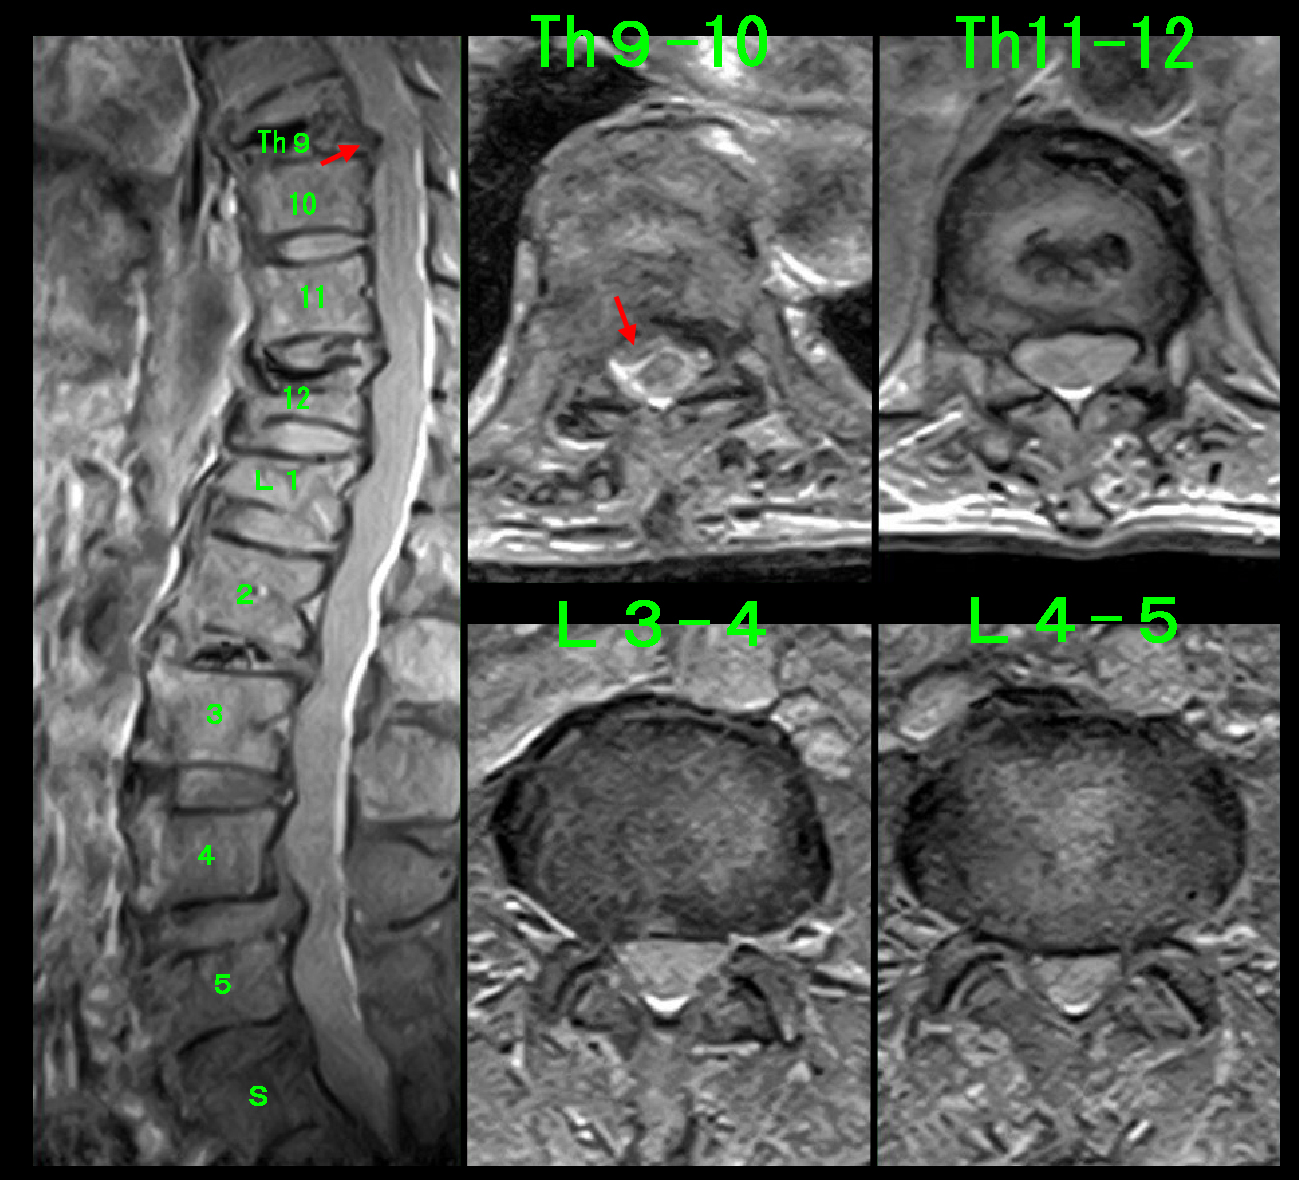

初診時MR.jpg

初診時の腰椎MRI検査では第12胸椎がつぶれために脊髄を圧迫するようになった所見が確認されました。

患者さんの腰痛は圧迫骨折発症後に続いているのですから、圧迫骨折により発症したTh11-12での脊髄圧迫が腰痛の原因であろうと推察しました。